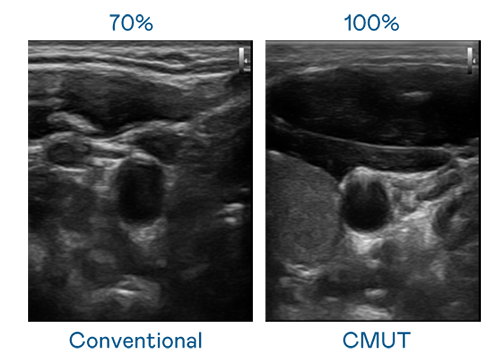

CMUT 技术是一种用电容式微机电元件来产生超音波讯号的技术。与传统 PZT 压电式技术相比,CMUT 频宽增加 30%,更宽频的超音波讯号让影像解析度大幅提升,是实现高影像品质医疗超音波扫描、促进精准医疗发展的关键技术。

大频宽带来超清晰影像

超音波影像的解析度高低,首先取决于探头能发出的讯号频宽。EVO真人视讯 CMUT 可提供高清晰的超音波讯号,提供高频宽、高灵敏度、影像纹理细节更高的超音波影像,协助医护人员缩短影像判读时间及利用精准的医疗影像进行诊断。